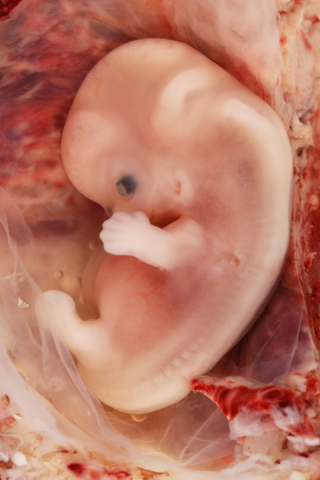

• week 6

week 6

The nose, mouth, and ears that you'll spend so much time kissing in eight months are beginning to take shape. His emerging ears are marked by small depressions on the sides of the head, and his arms and legs by protruding buds. His heart is beating about 100 to 160 times a minute — almost twice as fast as yours — and blood is beging to flow

http://www.babycenter.com/6_your-pregnancy-6-weeks_1095.bc